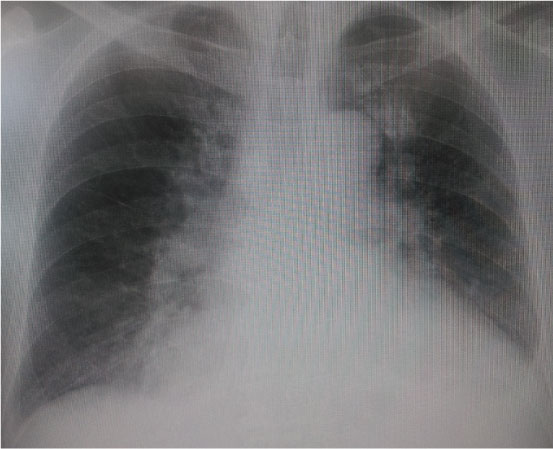

胸部Xp:CTR 71%, 肺うっ血(+), CPA鈍